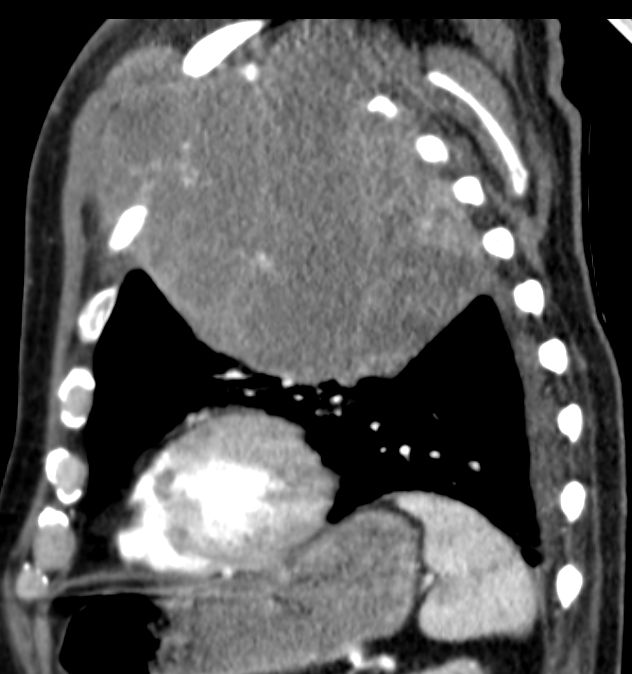

| Thoraxwanddestruktion | Plattenepithelkarzinom des rechten

Lungenoberlappens mit Destruktion der Thoraxwand und mediastinalen

Lymphknotenmetastasen. ![]() |